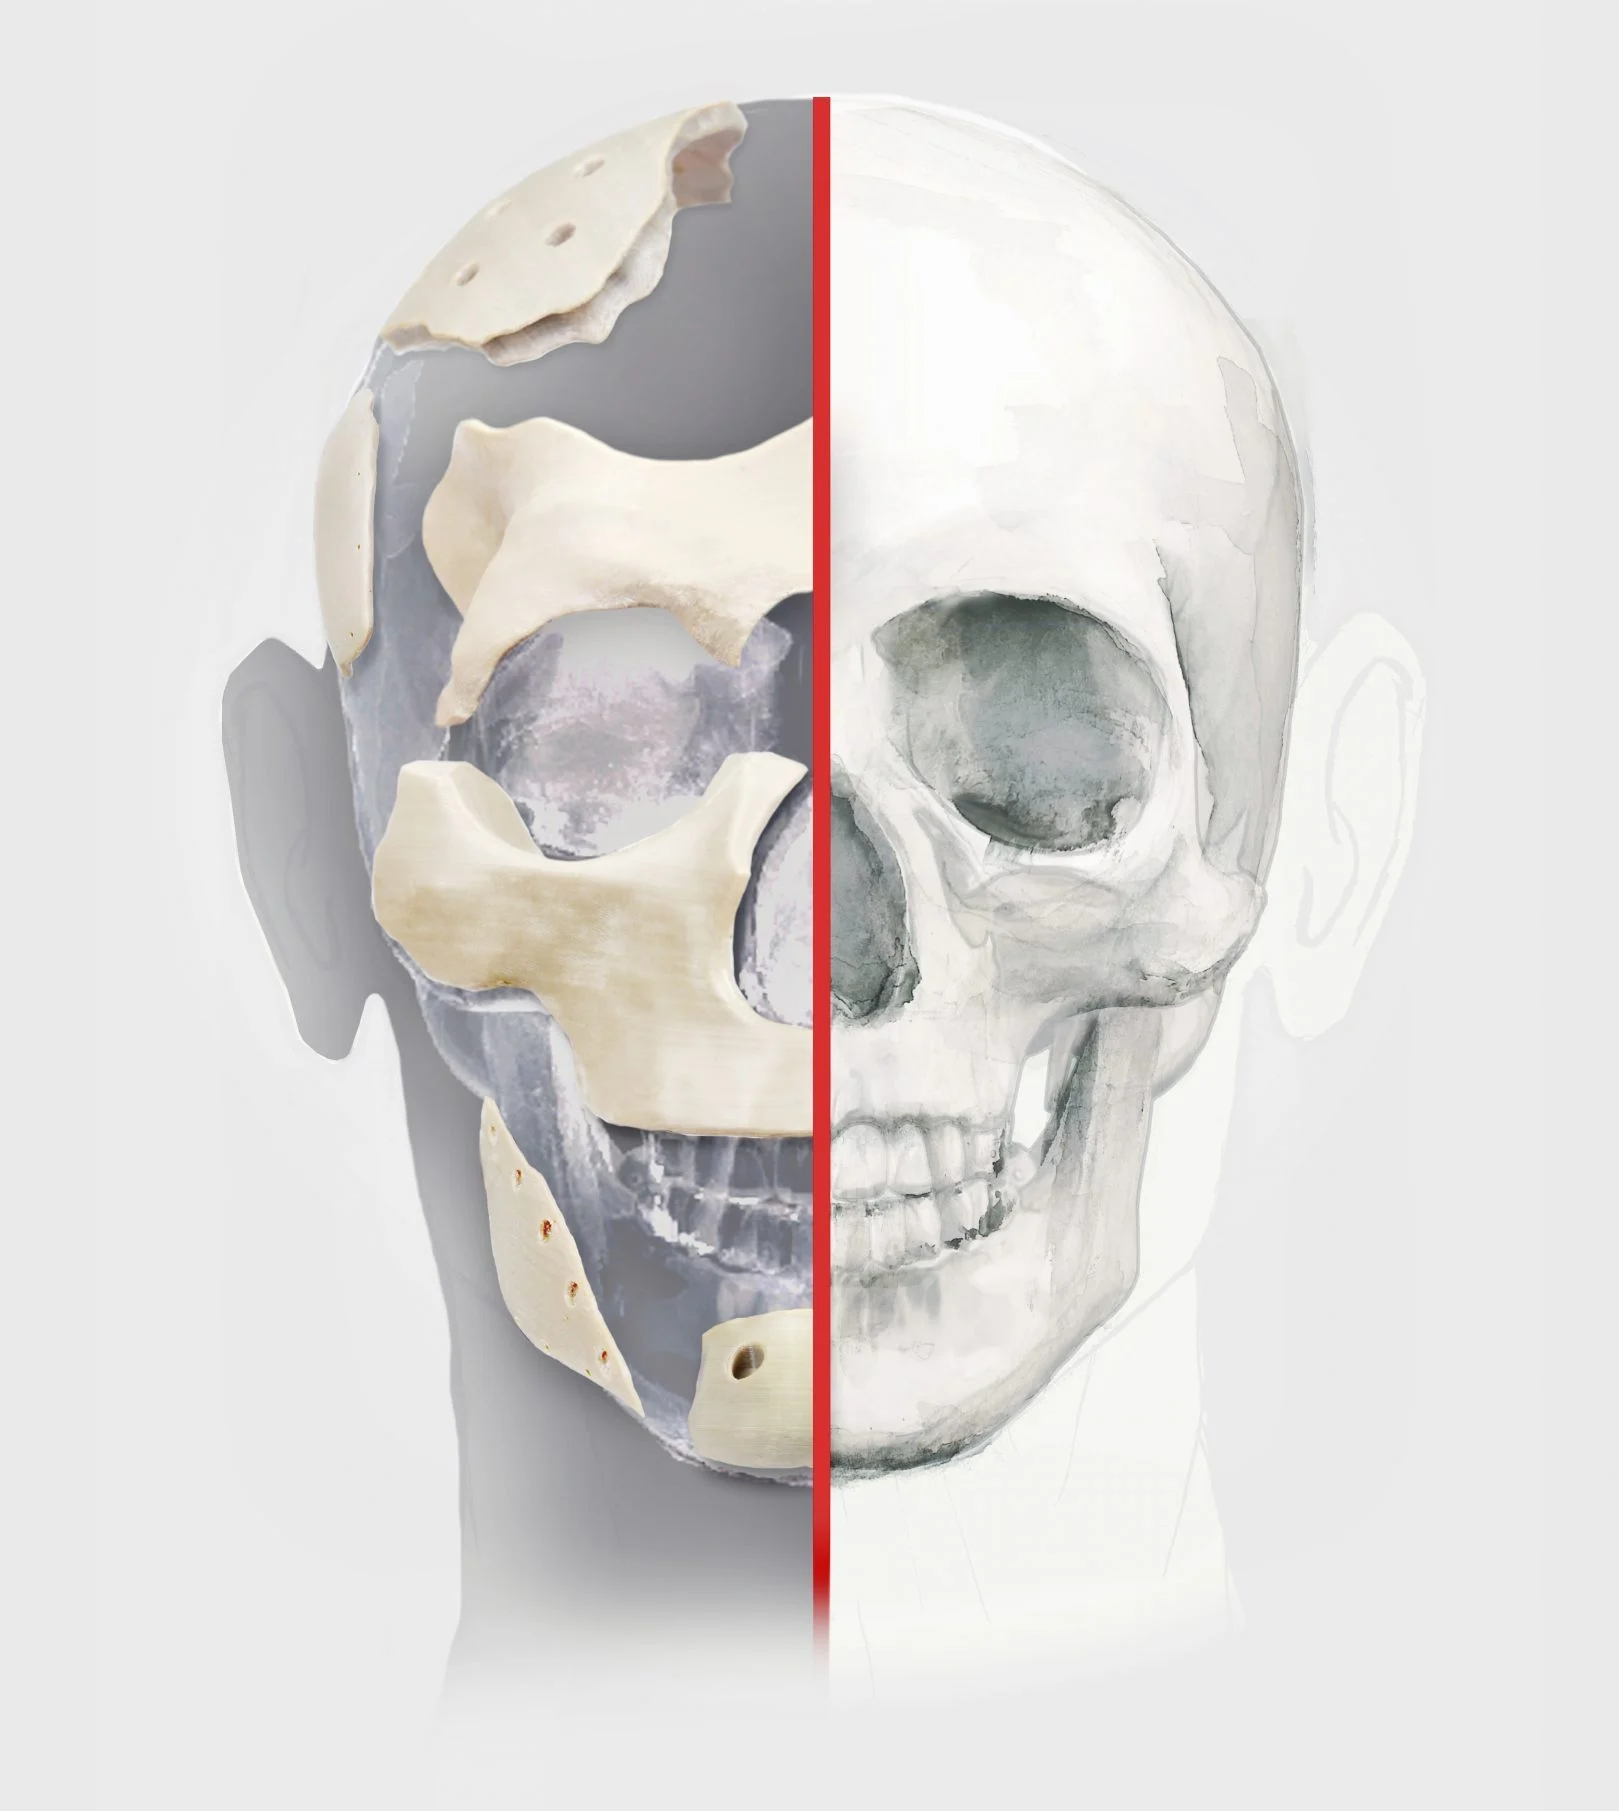

C Fix Patient-specific PEEK implants are the latest & best in class solution for cranial reconstruction in cranioplasty.

C Fix is designed in collaboration with neurosurgeons & made to fit the specific requirement of a patient. It is manufactured considering each patient’s anatomy and intraoperative adaptation & ease of use. Anatomical perfection is the goal of reconstruction surgery & C Fix helps achieve that.

Suits patient’s anatomy to give desired strength and aesthetics.

PEEK is the best biocompatible material at present.

Light weight yet bone-like strength.

Custom Cranial Implants are combined products of medicine, design, and engineering. It’s an example of a modern-day collaborative approach to addressing case basic solutions to patient needs. The goal is to have functionality & aesthetics with no compromise of one for the other.